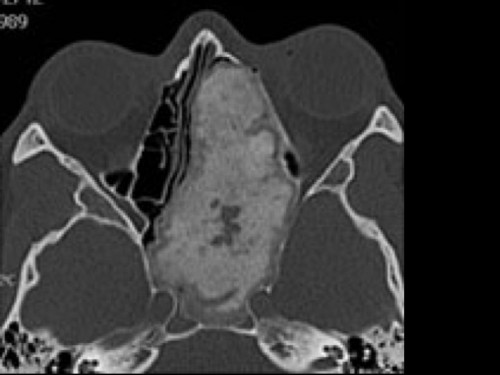

38 jähriger Patient. Seit neuestem Diplopie und immer wieder Kopfschmerzen. Seit er denken kann, vor allem beim Sport eine behinderte Nasenatmung.

Aus den CT Aufnahmen ist ersichtlich, dass ...

- Ader Tumor vom Clinoid ausgeht.

- Bes sich um einen gutartigen Tumor handelt.

- Ces sich um einen bösartigen Tumor handelt.

- Dder Tumor ossifiziert ist.

- Eer schon nach intrazerebral vorgewachsen ist.

Bildgebung - CT axial